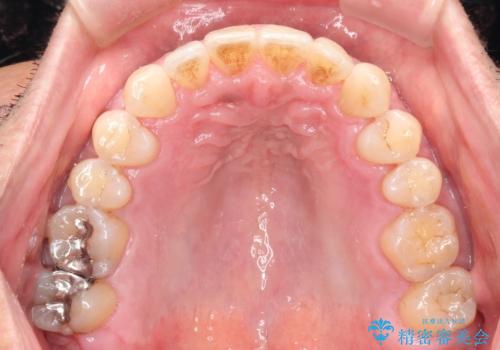

インビザライン invisalign ガタつきを治すマウスピース矯正

- 非抜歯・上顎臼歯遠心移動によるマウスピース矯正を計画した。

ガタつきを取り除くだけであれば非常に簡潔であるマウスピース矯正ですが、奥歯の位置関係の是正や、垂直的な歯の位置のコントロールなどが計画に含まれる場合、治療が難しくなってきます。